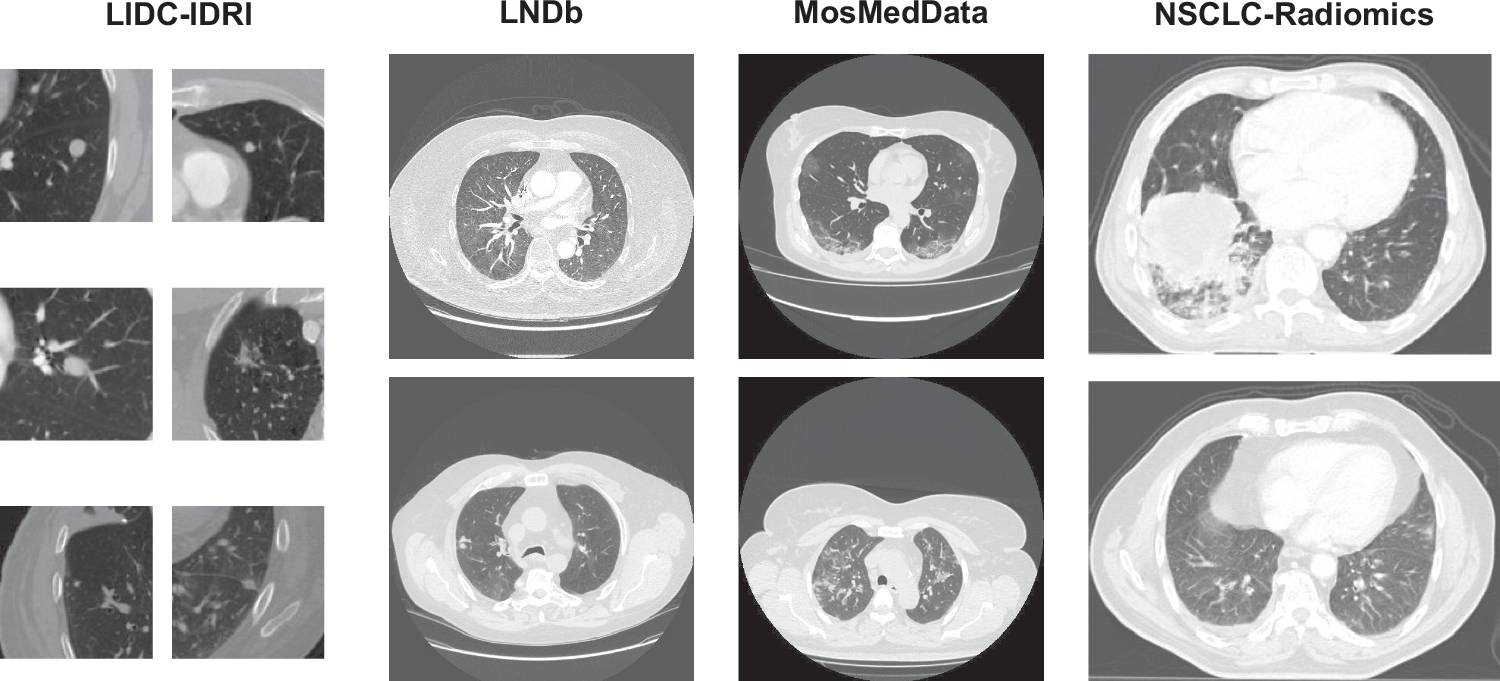

Fig. 1: Examples from the four evaluation datasets (LIDC-IDRI, LNDb, MosMedData, and NSCLC-Radiomics).

The significant visual differences in lesion appearance-ranging from small, well-defined nodules to large, complex tumors and diffuse infectious lesions-highlight the domain gap across the datasets, providing a robust benchmark for evaluating the model’s cross-domain generalization performance.